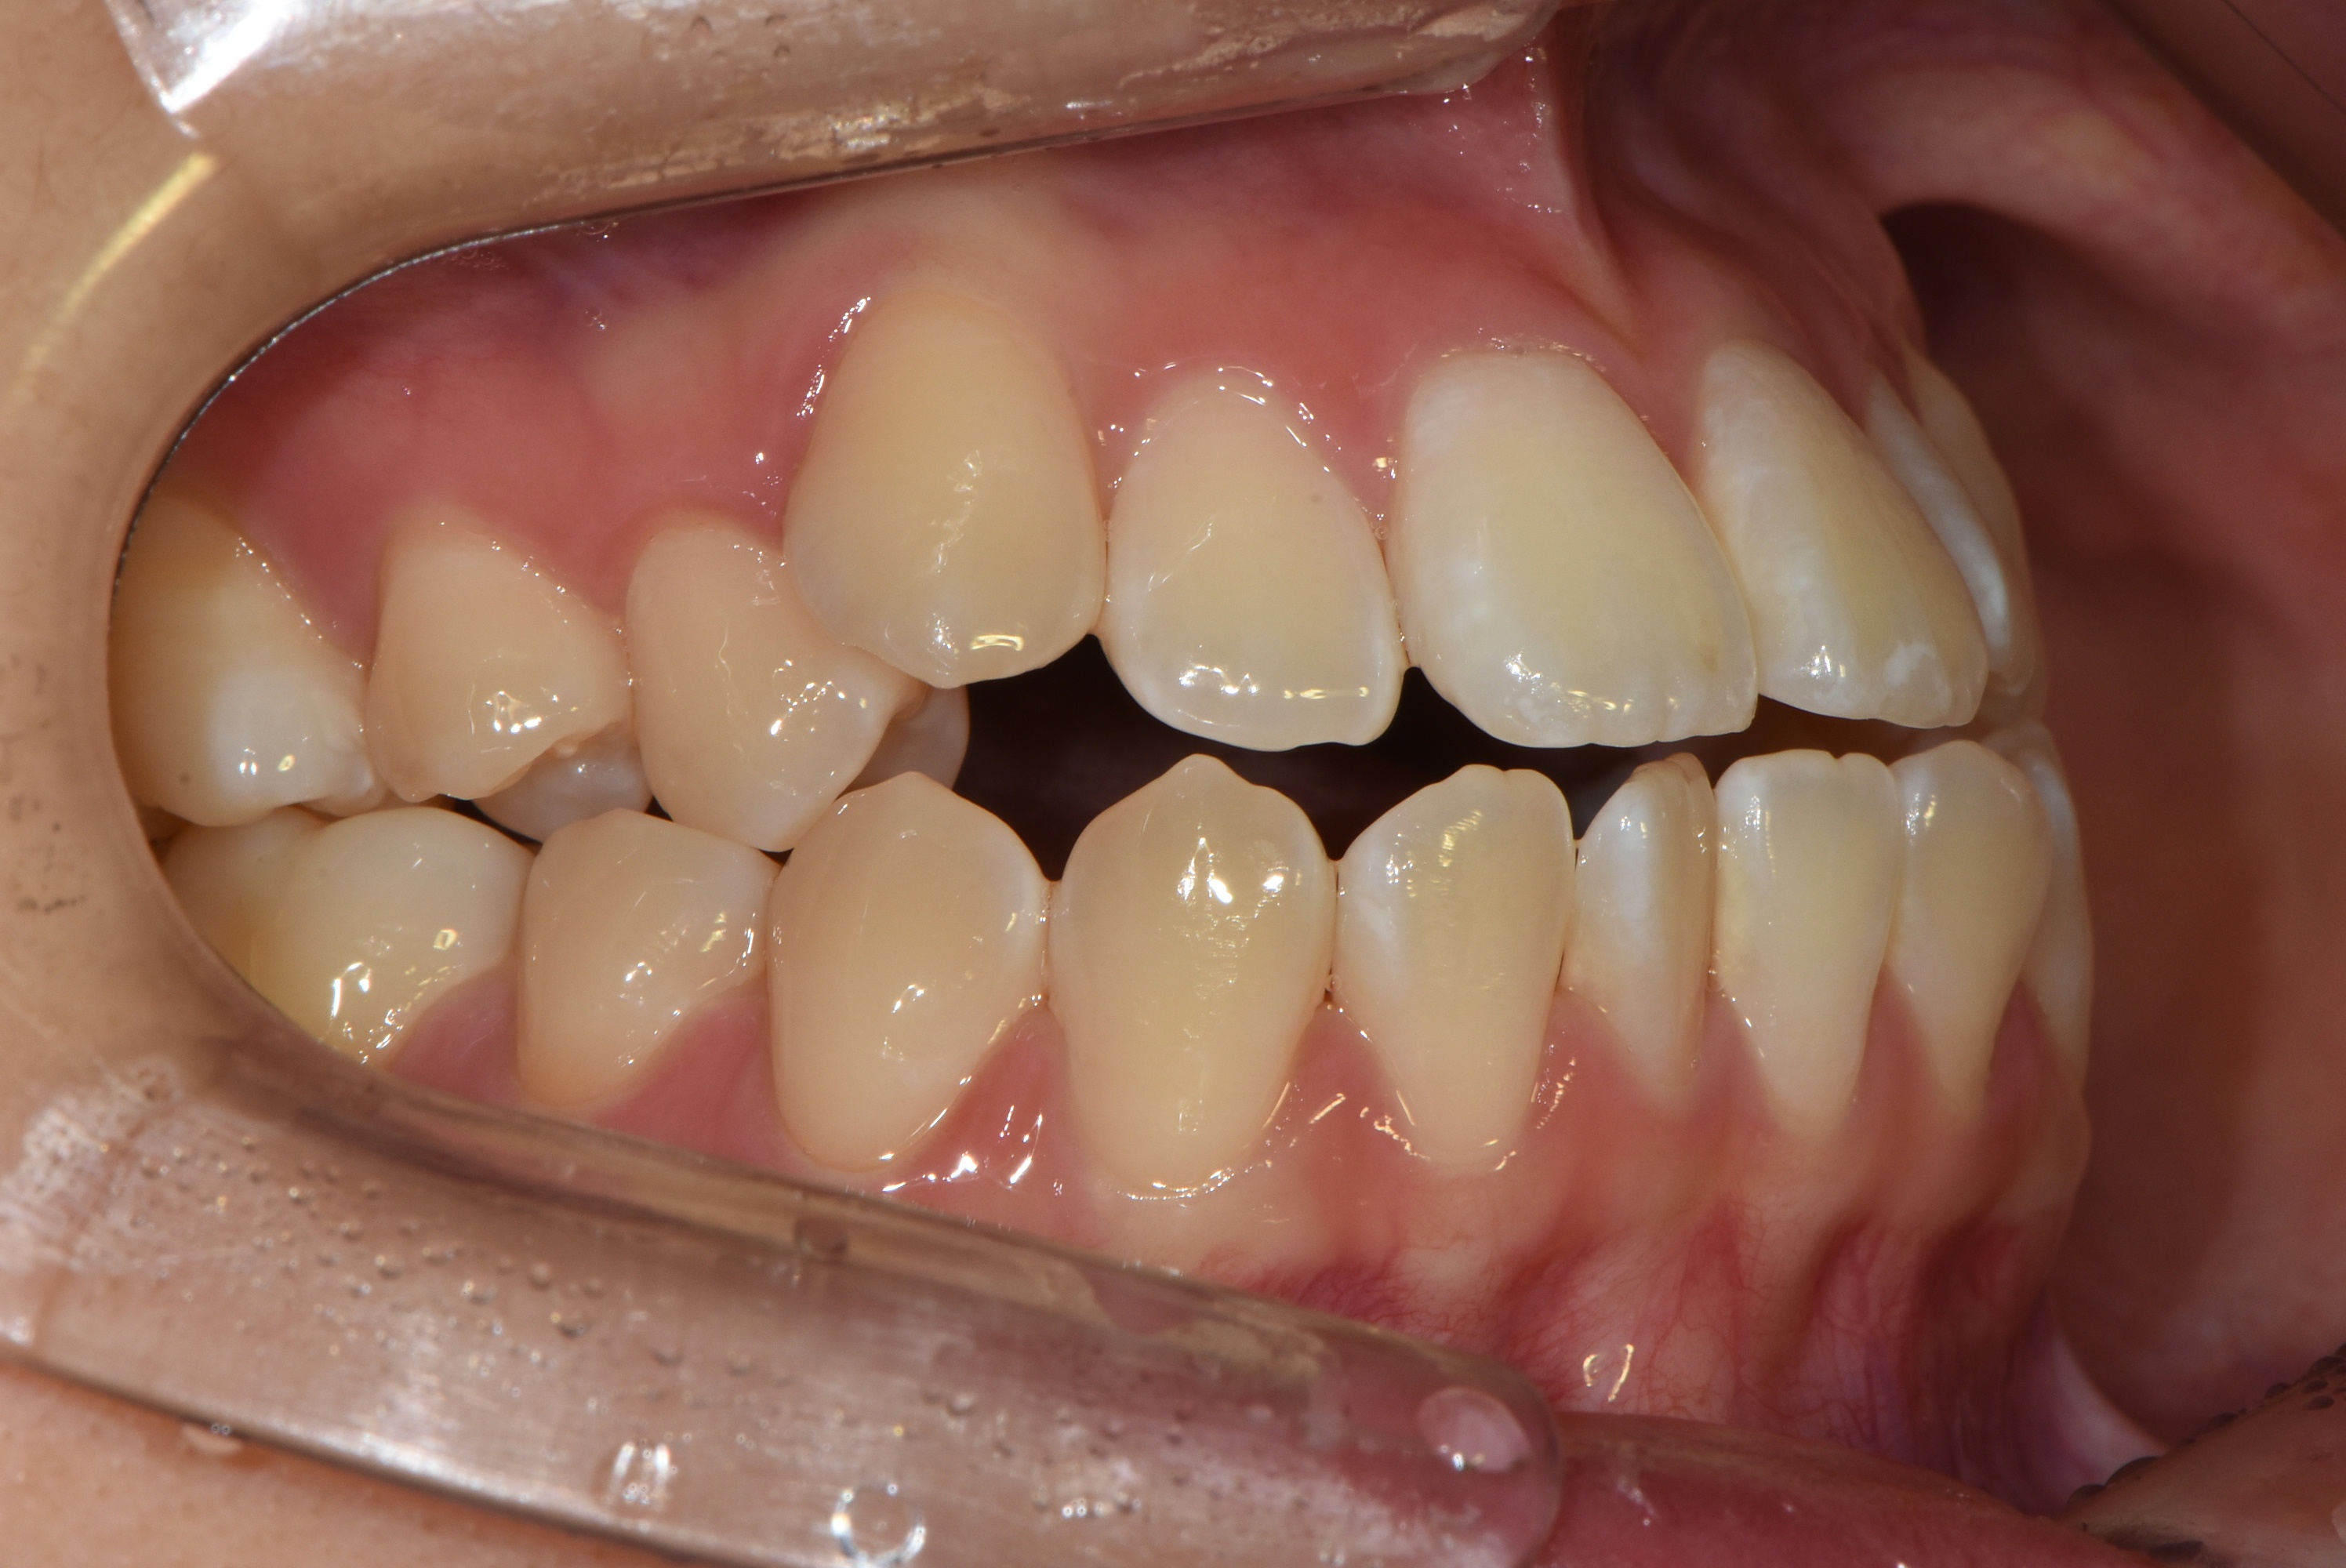

치료 전 사진입니다.